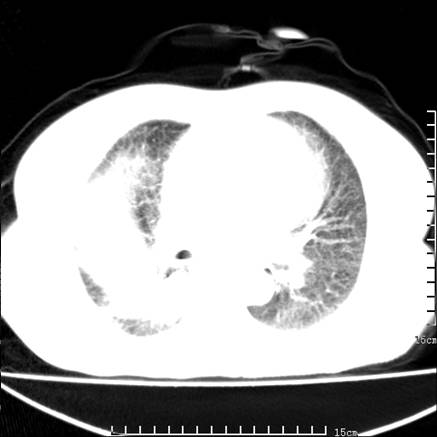

女,王某,58岁,咳嗽三个月余,基层医院二个月前诊为肺结核,用抗结核药二个月无明显疗效。

心包积液致肺瘀血.右侧周围型肺癌伴肺内转移,中间裂积液,叶间胸膜肥厚.右上肺大泡,右侧胸膜肥厚.

双肺继发型tb,心功能不全并肺淤血、心包、双侧叶间裂积液,肺大泡,右下胸膜肥厚钙化。